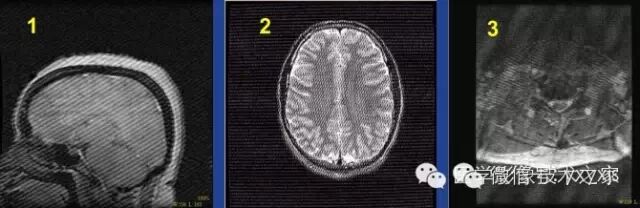

伪影特点:

覆盖整个图像的棘刺状伪影。可为单一方向,也可为多个方向相

交排列。可出现在序列的某一幅图像中,也可出现在整个序列。

1.单一方向--灯心绒伪影

2.两个方向--箭尾状伪影

3.多个方向,多组白噪声点复杂的伪影